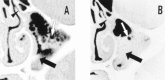

Results: Committee members agreed to adopt the term “rhinosinusitis” and reached consensus on definitions and strategies for clinical research on acute presumed bacterial rhinosinusitis, chronic rhinosinusitis without polyposis, chronic rhinosinusitis with polyposis, and classic allergic fungal rhinosinusitis. Symptom and objective criteria, measures for monitoring research progress, and use of symptom scoring tools, quality-of-life instruments, radiologic studies, and rhinoscopic assessment were outlined for each condition.